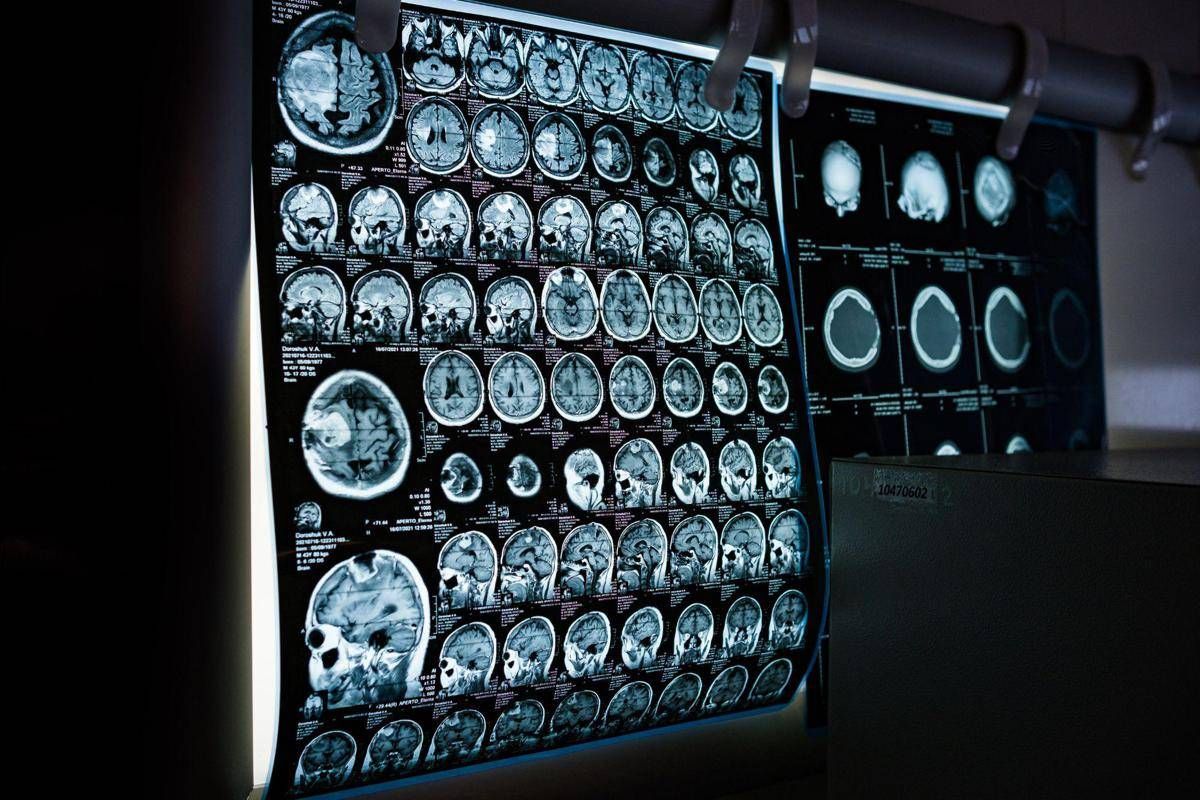

Uno spray nasale ferma l’invecchiamento del cervello, lo studio

Uno spray nasale testato sui modelli animali potrebbe invertire l’invecchiamento del cervello con sole 2 dosi, riducendo drasticamente l’infiammazione cerebrale, ripristinando le centrali energetiche cellulari del cervello e migliorando così significativamente la memoria. Un processo di ringiovanimento che agirebbe nel giro di poche settimane per durare mesi.

E’ il risultato dello studio condotto dai ricercatori della Texas A&M University (Naresh K. Vashisht College of Medicine) negli Stati Uniti. Lo spray contiene minuscole particelle biologiche note come vescicole extracellulari (Ev), che agiscono come veicoli di consegna con a bordo un potente carico genetico, i microRna. Le sostanze aggirano lo scudo protettivo del cervello e viaggiano direttamente nel tessuto cerebrale, dove vengono assorbite. Arrivati a destinazione nelle cellule immunitarie residenti nel cervello, i microRna ‘spengono’ i sistemi noti per essere responsabili dell’infiammazione cronica nel cervello che invecchia.

Per spiegare il senso di questo processo, gli scienziati invitano a immaginare il cervello come un motore ad alte prestazioni: nel corso dei decenni questo motore non solo si usura, ma inizia anche a surriscaldarsi. Piccoli ‘focolai’ di infiammazione covano nelle profondità del centro della memoria, creando una persistente nebbia mentale (brain fog) che rende più difficile pensare, formare nuovi ricordi o persino adattarsi a nuovi ambienti, aumentando al contempo il rischio di disturbi come il morbo di Alzheimer. Questo processo a lenta combustione viene chiamato neuroinfiammazione. E per decenni si è pensato che fosse il prezzo inevitabile dell’invecchiamento. Ma il nuovo studio, pubblicato sul ‘Journal of Extracellular Vesicles’, suggerisce che l’ondata infiammatoria potrebbe essere reversibile.

Il team guidato da Ashok Shetty, distinguished professor dell’ateneo e associate director dell’Istituto di medicina rigenerativa, insieme ai ricercatori senior Madhu Leelavathi Narayana e Maheedhar Kodali, ha sviluppato lo spray nasale e ha verificato che a livello cellulare il trattamento ha ricaricato i mitocondri neuronali, ovvero le centrali energetiche che si trovano all’interno delle cellule cerebrali. La terapia ha dissipato la nebbia mentale e ha anche migliorato fisicamente la capacità del cervello di elaborare e immagazzinare informazioni.

“Stiamo ridando vitalità ai neuroni riducendo lo stress ossidativo e riattivando i mitocondri del cervello”, evidenzia Narayana. Nei modelli trattati, i test comportamentali hanno confermato i risultati biologici, mostrando notevoli miglioramenti non solo nel riconoscimento di oggetti familiari, ma anche nell’individuazione di nuovi oggetti e di cambiamenti nell’ambiente circostante, in netto contrasto con il gruppo di controllo.

“Le malattie legate all’invecchiamento cerebrale, come la demenza, rappresentano un grave problema di salute a livello mondiale – sottolinea Shetty – Quello che stiamo dimostrando è che l’invecchiamento cerebrale può essere invertito, aiutando le persone a mantenere la mente lucida, a rimanere socialmente attive e a non subire il declino cognitivo legato all’età”. Lo studio suggerisce un’ampia applicabilità dello spray. I risultati del trattamento, illustra Shetty, “sono stati coerenti e simili in entrambi i sessi”. La modalità di somministrazione “è uno degli aspetti più interessanti del nostro approccio”, commenta Kodali. “La somministrazione intranasale ci permette di raggiungere e trattare il cervello direttamente, senza ricorrere a procedure invasive”.

Quanto agli effetti, quella che si osserva è “l’attivazione dei sistemi di riparazione del cervello, che guariscono l’infiammazione e si rigenerano”, suggerisce Shetty. Sono ovviamente necessarie ulteriori ricerche per confermare questi risultati, ma Shetty e il suo team hanno già depositato un brevetto negli Stati Uniti per la terapia. Il lavoro è stato portato avanti con il sostegno del National Institute on Aging (Nia).